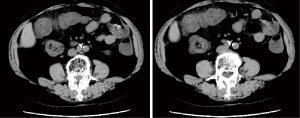

A 74-year-old female patient was admitted to the Department of Gastrointestinal Surgery in June 2021 due to “bleeding in stool for 1 day.” The blood stool (approximately 100 mL) was dark red, and the patient also complained of pain in the lower abdomen. The patient had a history of ITP and hypertension, who took prednisone acetate tablet and vincristine for ITP treatment, as well as nifedipine controlled release tablet and perindopril for hypertension treatment. Her white blood cell (WBC) count was 17.7×109/L, her hemoglobin (Hb) was 134 g/L, her platelet count was 21×109/L, and her serum potassium was 3.39 mmol/L. Her liver and kidney function indexes were normal at admission. A colonoscopy was performed after admission, which revealed multiple ulcers of various sizes in the transverse colon and descending colon (see Figure 1A-1F). Next, the pathological findings suggested chronic inflammatory cell infiltration, but no crypt, and no epithelioid granuloma. Subsequently, abdominal computed tomography (CT) was performed, which revealed the thickening of the hepatic flexure and transverse colon wall, decreased density, rough serosal surface, and exudation of the surrounding fat (see Figure 2).

Next, the abdominal CT revealed that the transverse colon and colonic hepatic curvature were thickened and densified, the serous membrane surface was rough, and the fat exudation had improved. Subsequently, pulmonary artery computed tomography angiography (CTA) was performed, which suggested (Figure 4) multiple filling defects at the distal end of the right pulmonary artery, the distal end of the right upper pulmonary artery, the proximal end of each segment of the arteries, the dorsal segment of the right lower lung, the proximal branch of the basal segment of the artery, and the distal end of the left lower lobe of the basal segment. Thus, a diagnosis of pulmonary embolism was considered. Additionally, the thrombotic thrombocytopenic purpura (TTP) test results were negative.